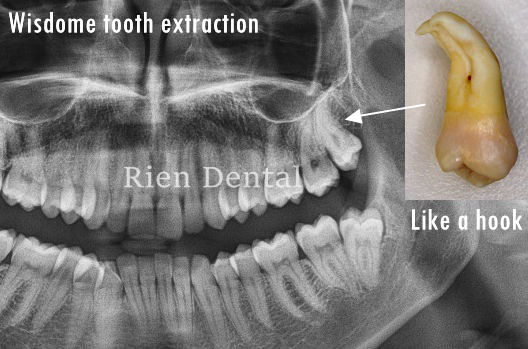

Wisdom tooth extraction

This wisdom tooth had a very curved root with root tips like hooks. The extraction was performed very carefully to avoid root fracture.